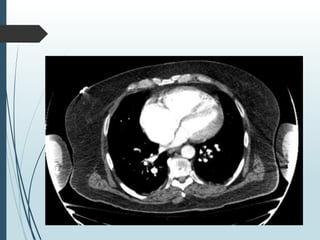

WCM Right and Left Heart Cath 4/2022

Off BIPAP on FI02 30%

 RA 22

 RV 110/20

 PA 104/45 mean 68

 PCWP 28

 AO 129/80 mean 96

 CO 7 L/min CI 3.2

 PVR 5.7 WU No Step up to suggest Shunt

 7.25/90/107 Hgb 17.9 Sat 95%

 Placed back on BIPAP post case

 Two vessel CAD TIMI 3 Flow 80% mid LCx,

 Tandom 80% RCA proximal and mid lesions

 Negative volume about 3 liters+ by this time